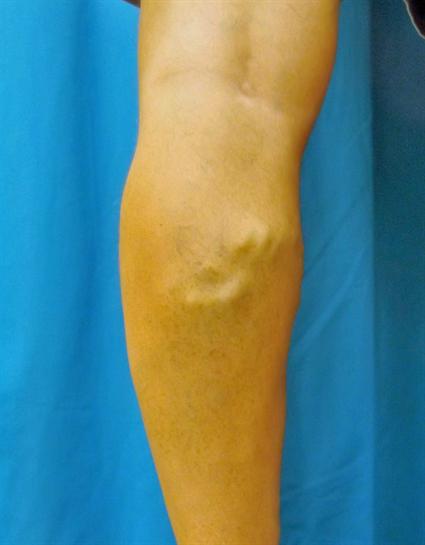

Endovenous Laser Ablation Case #273

Procedures Depicted: Endovenous Laser Ablation Radiofrequency Ablation Sclerotherapy

This 60 year old male suffered with aches, pain, tiredness, fatigue, cramps and restlessness in his left leg.  Standing 10 hours a day at his job was very difficult.  He was diagnosed with venous insufficiency of his left leg, which was treated with EVLA, VNUS Closure and echosclerotherapy.